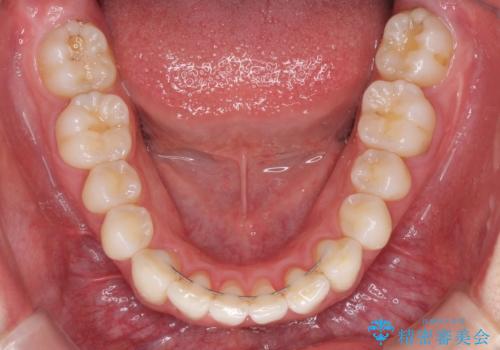

- 上下前歯の叢生を気にして来院された患者様です。

以前矯正をした後戻りということで、歯列不正はそれほど大きくなかったため、インビザライン・ライトを用いて矯正治療を行うこととしました。

インビザラインは1日に22時間を目安に装着していただきますが、装着時間が十分でないとシミュレーション通りに動かないことがあります。

前歯のデコボコが残っており、シミュレーション通りに動いていない部分がありましたが、再矯正であることやご本人の満足いくところまでデコボコが改善されたとのことで、治療を終了することとしました。